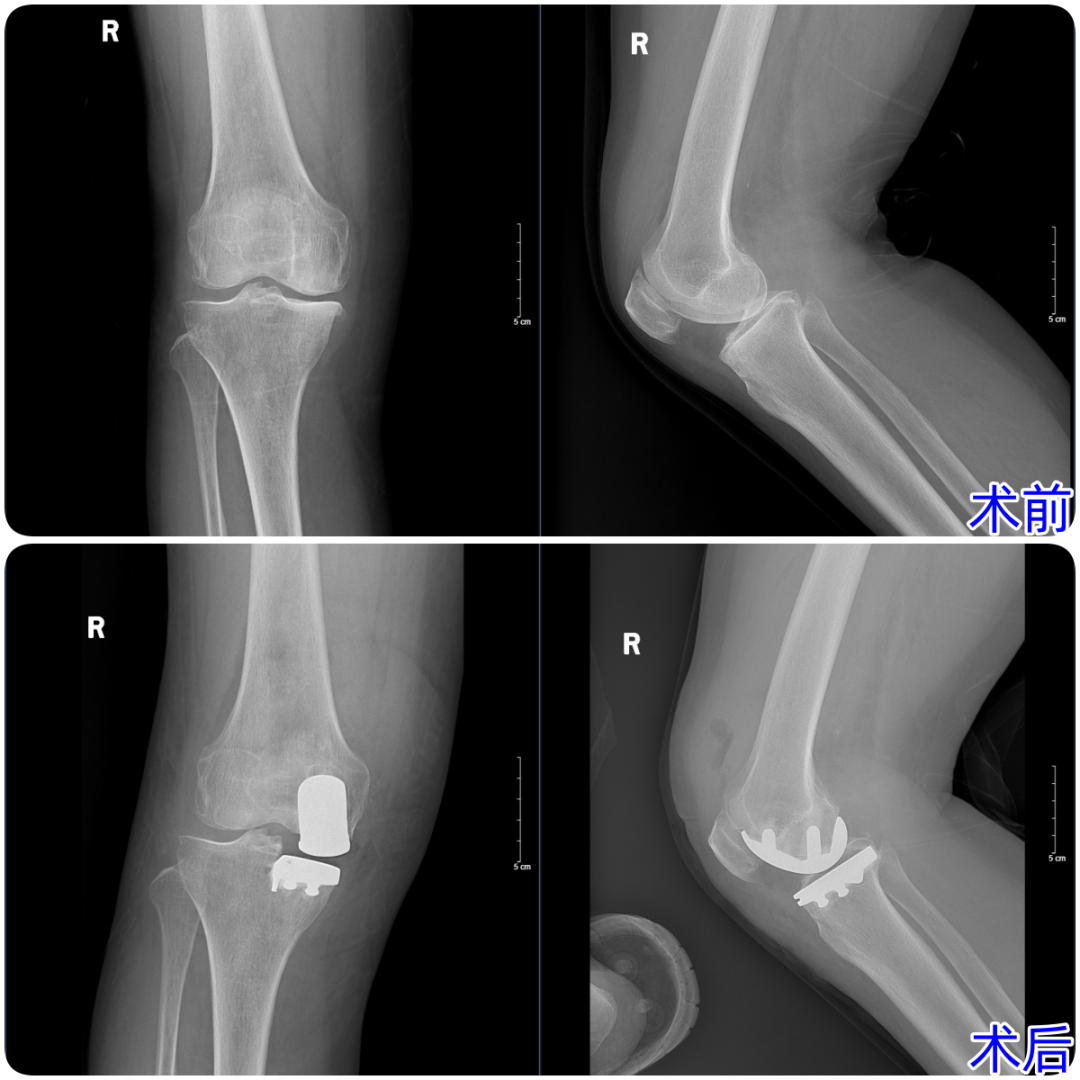

近日,济南南郊医院骨科杨学良主任团队成功为一名67岁右膝退行性骨关节炎患者实施膝关节单髁表面置换术,以"精准打击"替代传统全膝关节置换,术后恢复效果超预期,患者及家属高度认可骨科团队给出的治疗方案。

患者被右膝关节内侧疼痛困扰多年,近期症状急剧加重,走路、上下楼都成了难题。来到济南南郊医院检查后,诊断结果显示:右膝关节退行性变,关节间室狭窄,股骨髁和胫骨平台内侧边沿有骨赘的形成,股骨胫骨骨软骨炎、骨髓水肿。复杂的病情让老人和家人一度陷入焦虑——难道要接受创伤更大的全膝关节置换术?

杨学良主任团队针对患者的病情展开了细致的术前病例研讨。经过全面评估,团队认为患者的病变仅集中在膝关节内侧间室,符合单髁表面置换术的手术指征,无需进行全膝关节置换。这种“精准对病灶下手”的方案,既能解决疼痛问题,又能最大程度保留患者自身的膝关节功能,创伤更小、恢复更快。

在手术室与麻醉科的密切配合下,团队按照预定方案顺利实施手术。术中精准定位病变区域,仅对磨损的关节面进行置换,整个过程高效且精准。术后,患者的恢复情况远超预期。在医护团队的专业指导下,患者很快就能下地进行功能锻炼,膝关节疼痛明显缓解,活动度也逐步恢复。